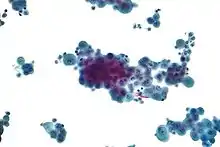

4. Cytopathology to identify cancer cells, but may also identify some infective organisms